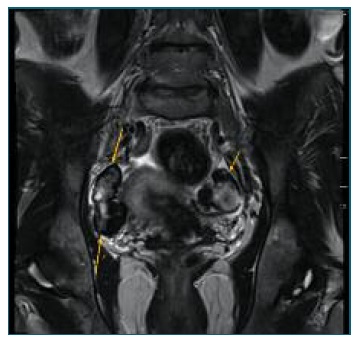

On MRI, the “black garland sign” refers to a marked T2 hypointense thick rim of fibrous tissue surrounding the ovary in the setting of ovarian fibromatosis2. The black garland appearance along with relative sparing of the central ovarian parenchyma helps to distinguish ovarian fibromatosis from other fibrous ovarian lesions including fibromas, fibrothecomas, and Brenner tumors2,5. On post-contrast imaging, fibromatosis demonstrates no significant enhancement in the parenchymal phase, owing to its fibrotic nature2.

A 44-year-old woman, nulliparous, with regular menses and a personal history of primary Sjogren Syndrome, arterial hypertension, sinus bradycardia, hyperparathyroidism and androgenetic alopecia consulted her gynecologist to clarify a clinical condition of pelvic pain associated with an approximately 1cm heterogenous solid adnexal mass, Color Score 1 was found on ultrasound. Further characterization of the mass through MRI demonstrated moderate enlargement of the ovaries with lobulated margins. The ovarian cortex was thickened and demonstrated a homogeneous low-signal intensity on both T1 and T2-weighted images, suggestive of fibrous tissue, with a “black garland” appearance and consistent with ovarian fibromatosis.

Figure 1 Black garland Sign. Axial T2-weighted image demonstrating a markedly T2 hypointense rim around the ovaries (right adnexa showed) without a central ovarian parenchymal mass. This hypointense rim is referred to as the ‘‘black garland’’ sign.